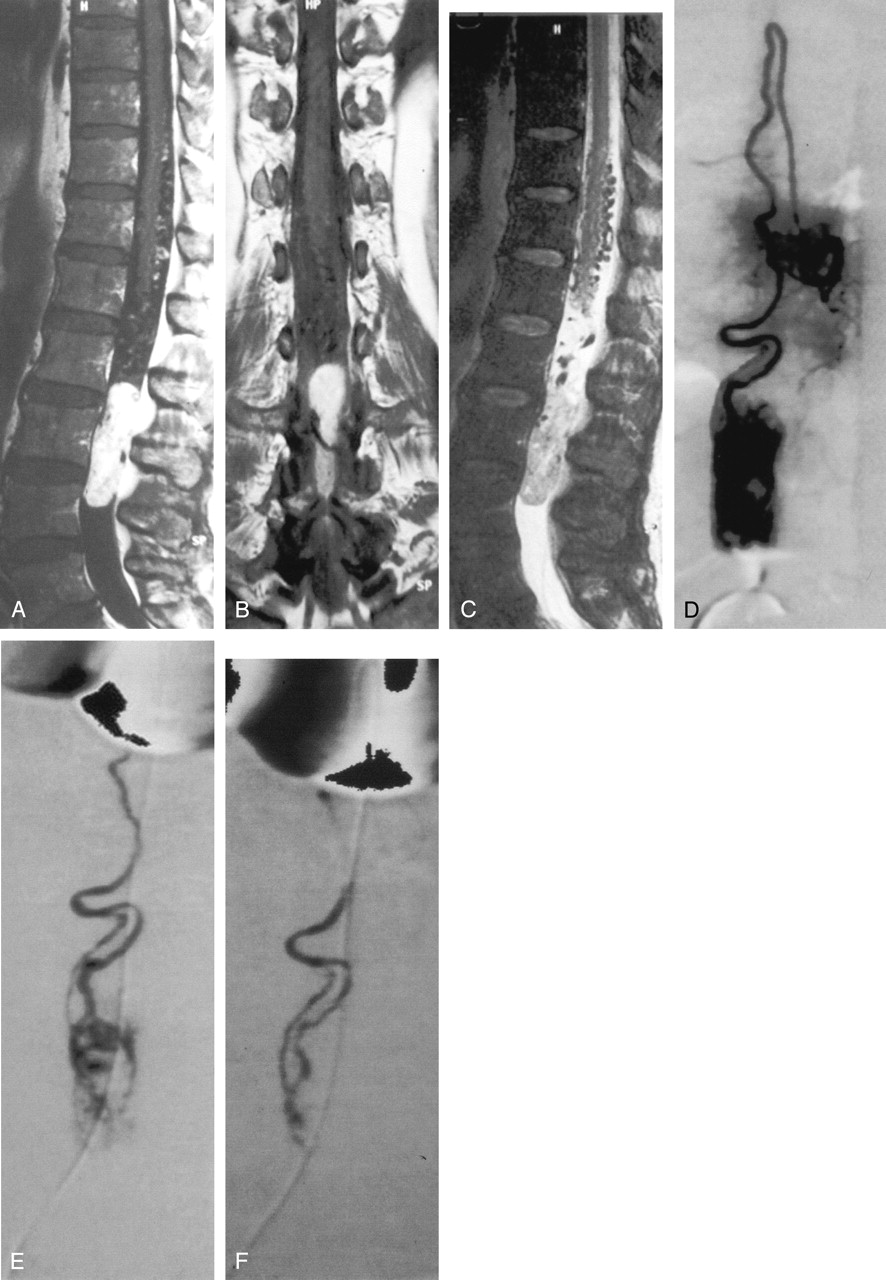

Case 3. Hemangioblastoma of the filum terminalis in a 61-year-old man.

Sagittal (A) and coronal (B) T1 MR images after administration of gadolinium show marked enhancement of the tumor located at level of L3 vertebral body. C, On sagittal T2 MR image, the lesion is predominantly isointense, heterogeneous with flow void due to high flow vessels. D, Angiography of left first lumbar artery shows that the tumor is fed by the anterior spinal axis. E, Intermediate step of embolization performed through the ASA (artery of Adamkiewicz) shows partial reduction of the tumoral blush. F, Final control angiography of the left first lumbar artery shows angiographic tumoral devascularization.